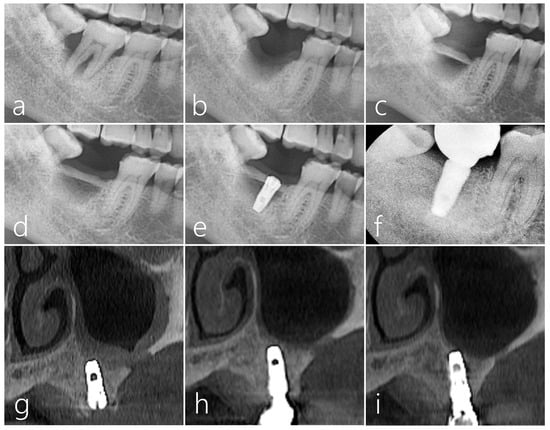

2.2. Case 2

2.4. Case 4